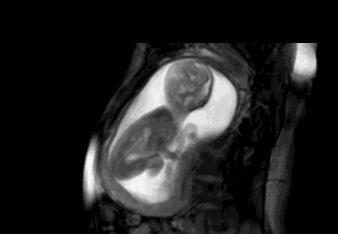

其实小家伙很小的时候就已经开始“闹腾”了:妥妥的一个运动健将!

小碎步向前缩,撅着小屁股用力一蹬,身体向后滑去——“母胎版蛙泳”动作很标准嘛!

▼

不行,刚才的动作不够标准,再来一次!

不过,力气好像还是太小了,算了,休息休息再说~